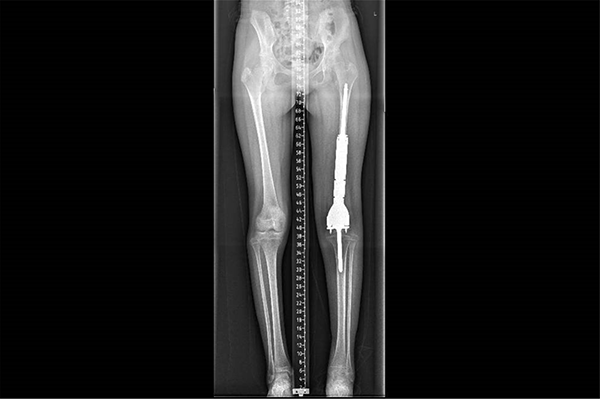

这是小鱼的术后X线影像

3D打印+可延长假体,精准重建护航未来成长

术后仅两周,小鱼便可在支具辅助下尝试负重行走。接下来,他还将完成后续化疗及系统性康复训练,逐步恢复肢体功能。